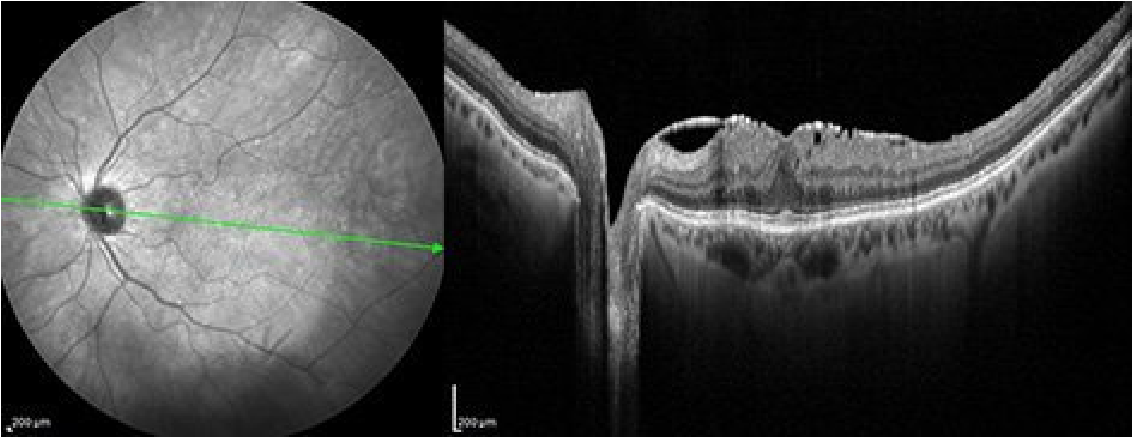

Tomografía de Coherencia Óptica de alta resolución que permite analizar en detalle la estructura de la retina y con ello orientar el pronóstico de manera precisa en una paciente con membrana epirretiniana.

Tomografía de coherencia óptica de alta resolución y de campo amplio que muestra una membrana epirretiniana en la superficie de la mácula que distorsiona la estructura de la retina.